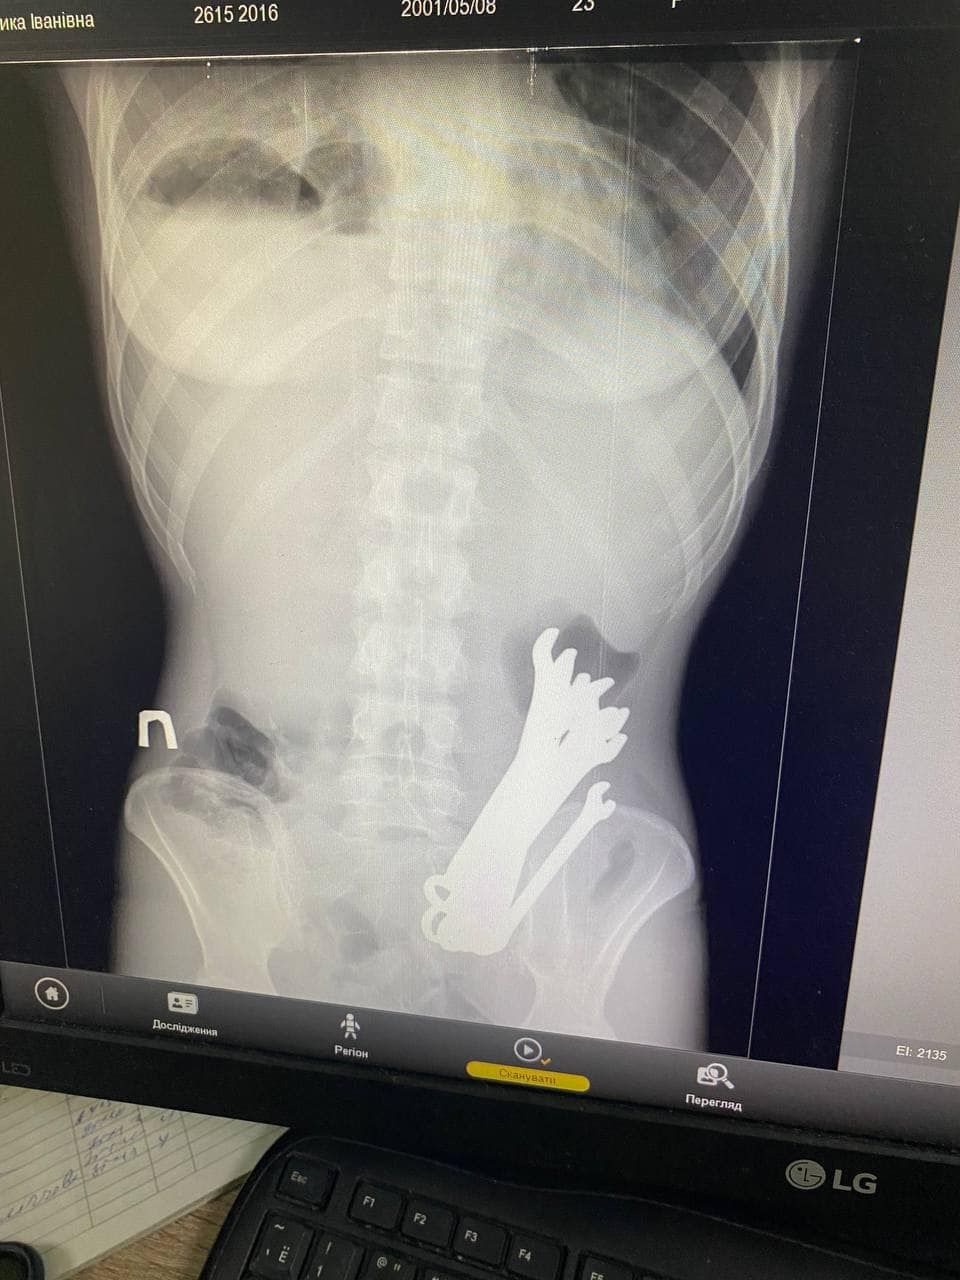

Медики госпитализировали пациента с вблизи проблем, в частности, тяжелым воспалением шеи, разрывом пищевода, воспалительным процессом в клетчатке средостения (участок в грудной полости), гнойным воспалением плевры, инородными телами и опущением желудка.

«Врачами выделения одномоментно выполнено цервикотомию с левой стороны, правостороннюю торакотомию с медиастинотомией, верхне-срединную лапаротомию, гастротомию с наложением гастростомы», – рассказали в отделении больницы.

В организме мужской элемент обнаружили 6 гаечных ключей / Фото Черкасской районный больницы